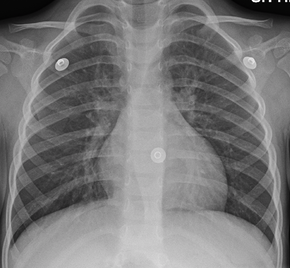

Mild peri hilar cuffing as seen in viral bronchitis

A physical examination will often reveal decreased intensity of breath sounds, wheezing, rhonchi, and prolonged expiration. Most physicians rely on the presence of a persistent dry or wet cough as evidence of bronchitis.[citation needed]